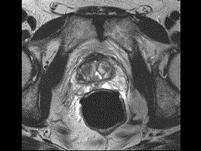

问题 男性,66岁,排尿困难多年,现感会阴部疼痛3个多月,指肛检查触及前列腺表面不规则,行MRI检查,如图所示,你认为最可能的诊断是()

选项 A.前列腺增生 B.正常前列腺 C.前列腺癌 D.前列腺钙化 E.前列腺出血

答案 C